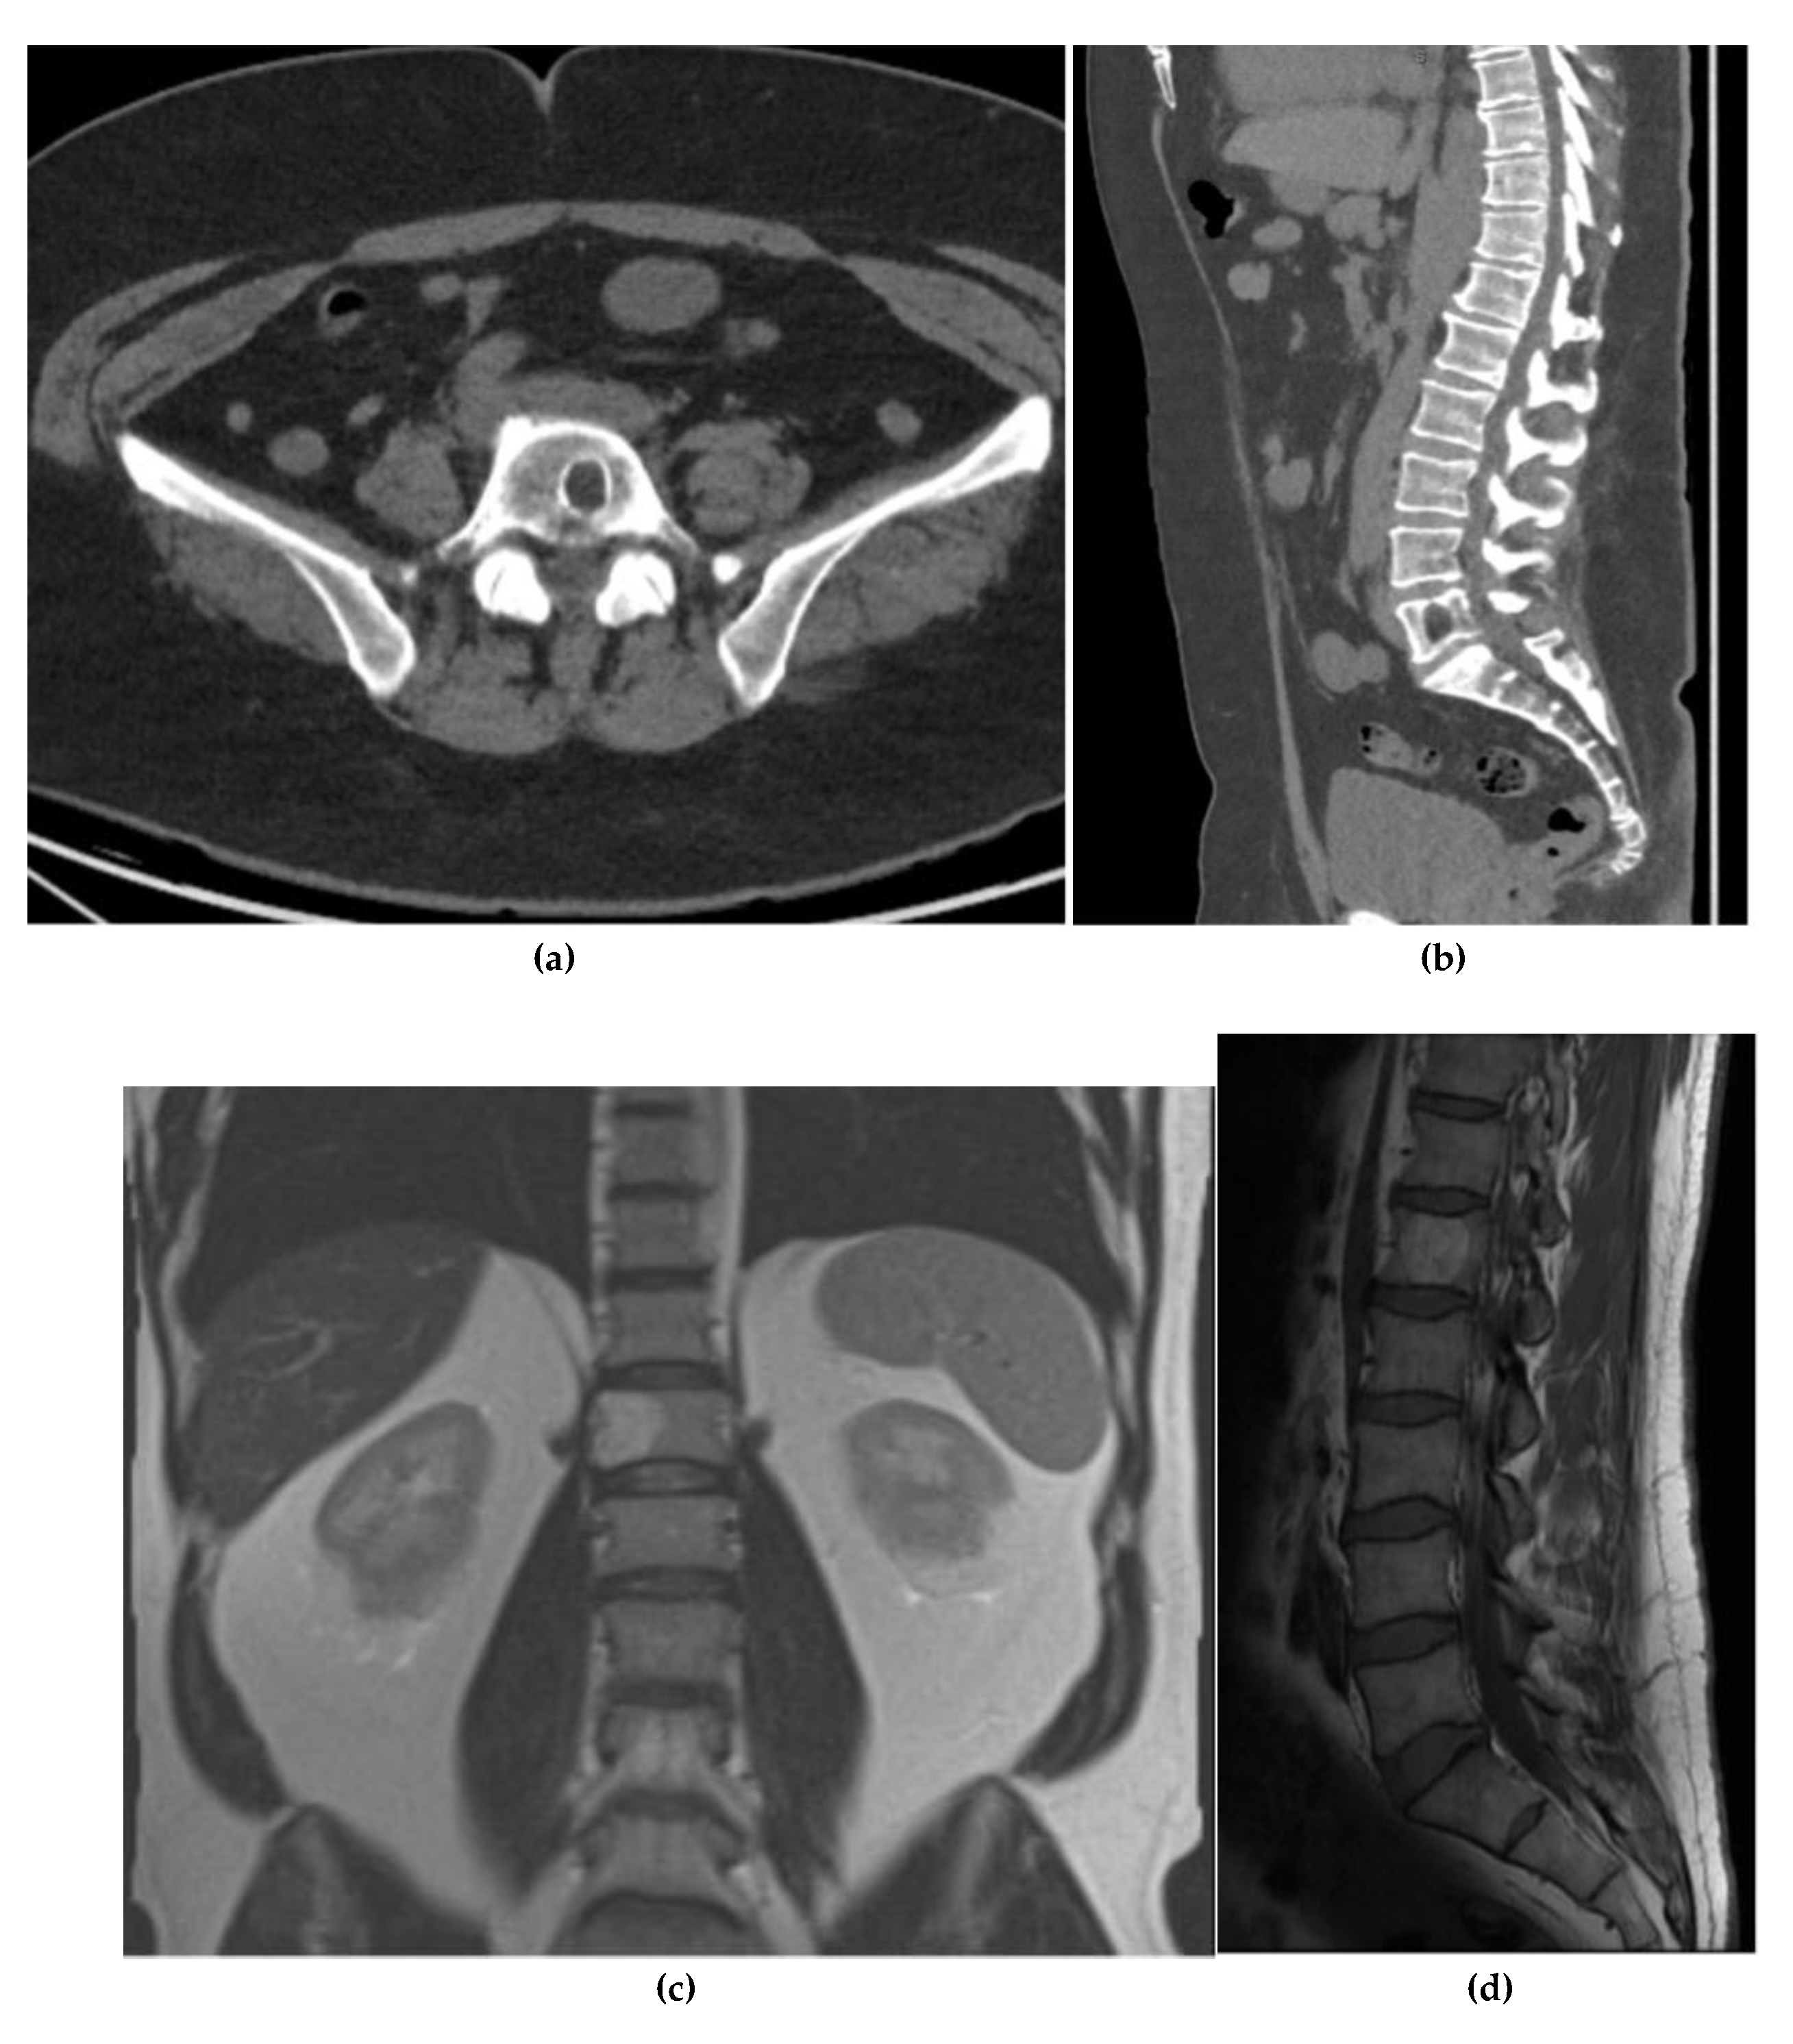

Chordoma